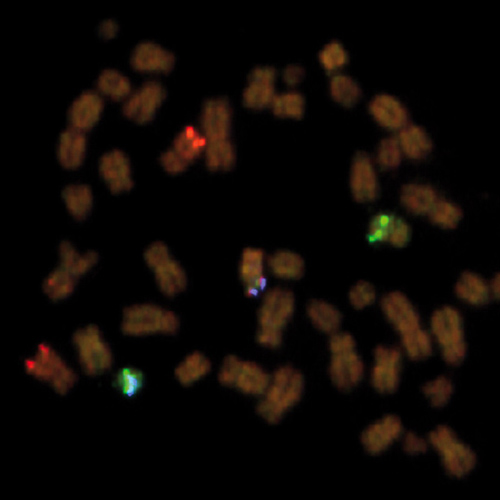

KBI-10503

1q21 / 8p21